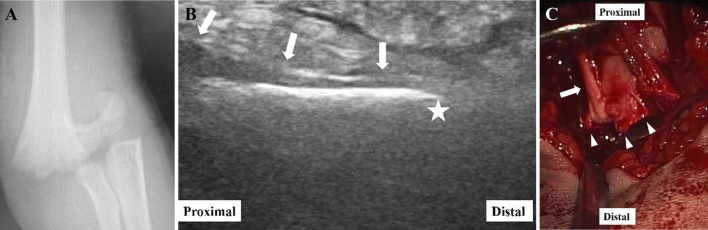

Fig. 2.

Case 1: 5-year-old boy with complete radial nerve palsy. a Anteroposterior X-ray showed a Gartland type III supracondylar humerus fracture. b The longitudinal sonography of the radial nerve (white arrows) showed the nerve became thinner as it got close to the fracture site and suddenly disappeared at the fracture site (white star). The nerve appeared hypoechoic and had a loss of the normal fibrillar pattern. c Operative findings showed the radial nerve (white arrow) was entrapped by spikes (white arrow heads) of the edge of the proximal fragment and was tightly bent about 90° in the posterior direction

On the other hand, in the P group, three cases with supracondylar humerus fractures (Cases 1–3) had abnormal radial nerve observations. The radial nerve was in contact with the volar surface of the cortex of the proximal humeral fragment. It became thinner as it approached the fracture site and suddenly disappeared at the fracture site. In addition, the nerve appeared hypoechoic and had a loss of its normal fibrillar pattern (Fig. 2b). The radial nerve in two of three cases of humerus diaphyseal fracture (Cases 4, 5) was visualized from the proximal to the distal region of the fracture site. However, it was compressed by the edge of the distal humerus fragment from the bottom and flattened at the fracture site. In addition, the nerve appeared hypoechoic and had a loss of its normal fibrillar pattern around the fracture site (Fig. 3b). In these five cases, SSRNE was performed, and these findings were compared to the sonographic findings. However, in the other case of humerus diaphyseal fracture (Case 6) and the case of elbow dislocation (Case 7), the radial nerve was swelling (Fig. 4b) compared to the opposite side (Fig. 4c), but it had a normal fibrillar pattern and no compression along it (Fig. 4b). In these two cases, SSRNE was not performed and sonographic reevaluation of the radial nerve after ORIF or CRIF (intramedullary nail fixation in Case 6) confirmed no change in the condition of the radial nerve from these procedures. Details are shown in Table 1.

In Group C, five of six cases of humerus diaphyseal fracture cases (Cases 13–17) received ORIF depending on the backgrounds of each case such as age and fracture type, although sonographic findings of the radial nerve were judged as normal. In four of these five cases (Cases 13–16), the radial nerve was observed to reach the fracture site directly from the posterior approach, and the macroscopic findings of the nerve corresponded with sonographic findings in these cases. In Group P, SSRNE was performed in five cases with radial nerve palsy (Cases 1–5). The operative findings corresponded with the sonographic findings in all five cases. In the three cases of supracondylar humerus fracture (Cases 1–3), the radial nerve ran along the volar cortex of the proximal humerus fragment from the proximal side, was entrapped by spikes of the fragment edge, and was tightly bent about 90° to the posterior direction. However, no rupture of the nerve was observed. Therefore, we resected the fragment spikes and exfoliated the radial nerve from the surrounding soft tissue distally to Frohse’s arcade to loosen the tension of the nerve and release it from the entrapment (Fig. 2c). In two cases of humeral diaphyseal fracture (Cases 4, 5), the radial nerve had no entrapment; however, it was compressed by the edge of the distal fragment from the bottom (Fig. 3c). Details are shown in Table 1.